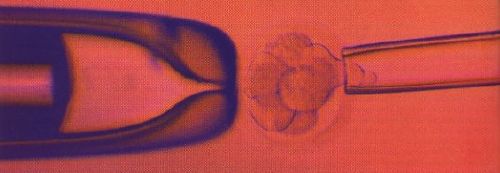

Im Dezember 1998 hatten amerikanische Forscher erstmals darüber berichtet, dass es ihnen gelungen sei, stabile Kulturen von menschlichen embryonalen Stammzellen anzulegen. Das war eine Sensation, wie auch die bald darauf folgende Erkenntnis, dass erwachsene Stammzellen, wie sie sich etwa im Knochenmark finden, gezielt in bestimmte andere Zellen verwandelt werden können. Stammzellen sind die Quelle aller rund 50 Billionen Zellen unseres Organismus. Als unreife Zellen, denen beim Embryo noch alle, beim Erwachsenen viele Entwicklungsmöglichkeiten off]en stehen, können sie sich im Laufe der Zeit zu spezialisierten Zellen für Muskeln, Nerven oder Haut ausdifferenzieren. Sie sind gewissermaßen der Jungbrunnen des Lebens, aus dem die Medizin der Zukunft Ersatz für Patienten mit vielerlei degenerativen Krankheiten zu schöpfen hofft. Humane embryonale Stammzellen (HES) haben das größte Entwicklungspotenzial. Sie werden aus wenige Tage alten Embryonen gewonnen, die nach einer künstlichen Befruchtung übrig geblieben sind. Wie und ob sich das therapeutische Potenzial von Stammzellen verwirklichen lässt, ist ungewiss. Deutlich ist dagegen das grundsätzliche ethische Dilemma: Dürfen wir Embryonen zerpflücken oder herstellen, um sie für Forschungszwecke zu verwenden? Dürfen wir einen solchen Eingriff verbieten, auf dessen Grundlage sich eventuell das Leben vieler Menschen retten lässt? Und: Könnten mit erwachsenen Stammzellen, den adulten Stammzellen, nicht die gleichen Ergebnisse erzielt werden? Ist ein fünf Tage alter Embryo lebendig oder nur ein lebloser Zellhaufen? Wann beginnt das Leben? - eine Frage, zu der führende Wissenschaftler - Genetiker, Biologen, Mediziner - aus den USA, Frankreich, der Schweiz, Japan, Großbritannien und Deutschland Stellung nehmen.

Ich schreibe einer Ansammlung von Zellen im Reagenzglas, die durch Befruchtung im Labor entstand, nicht den Status menschlichen Lebens zu. Das Schicksal dieses Zellhaufens unterliegt der freien Entscheidung verworfen zu werden, durch die Frau und den Mann, die zu seiner Entstehung beitrugen"

Es beginnt eindeutig mit der Befruchtung. Aber ein menschliches Wesen entsteht dabei nur der Möglichkeit nach. In vielen Fällen und selbst bei der Mehrzahl der auf normalem Weg erfolgten Befruchtungen bleibt der Erfolg aus. Die meisten Embryonen entwickeln sich einfach nicht, und das nicht nur, weil es zu einer Fehlgeburt kommt, sondern auch schon vor der Implantation. Bei der In-vitro-Fertilisation werden zahlreiche menschliche Embryonen erzeugt. Die überschüssigen werden entweder in flüssigem Stickstoff aufbewahrt, oder aber, und das ist der Normalfall, man spült sie buchstäblich durch den Ausguss. Da muss man sich doch ernsthaft fragen, ob es nicht besser wäre, sie für sinnvolle Forschung zu verwenden"